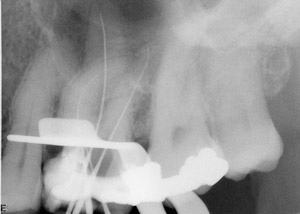

In the following case, the author used several of the above suggestions to properly determine working length. This tooth was diagnosed with irreversible pulpitis, and multiple visits were required to complete the case. While the maxillary sinus and zygoma often interfered in the author’s interpretation of the tooth’s anatomy, the tooth’s anatomy itself proved to be the largest obstacle to performing ideal root canal therapy (Figure 1). Originally, a periapical radiograph was taken to determine if the mesial canals actually curved as severely as the hand files had indicated. A periapical radiograph was then taken to approximate the measurements (Figure 2). Just from his own tactile sensation, the author came close to approximating the proper length of the canals but was not entirely accurate.

Figure 2 An approximate working-length radiograph.

Using the Foramatron, a length measurement was taken to determine precise working length. This apex locator is particularly easy to use because its display allows for good visibility of when canal length has been properly achieved. It is also straightforward, accurate and technique-friendly for both the advanced clinician as well as those using an apex locator for the first time.